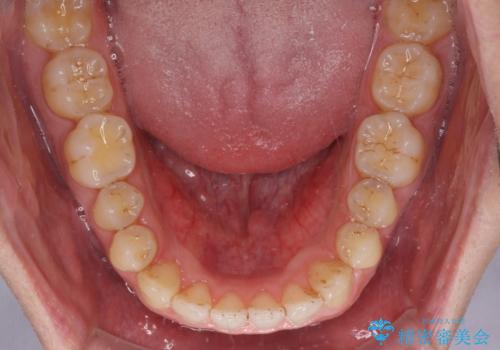

- 上の前歯の隙間を気にして来院された患者様です。

インビザラインにより、上下の歯列を側方に拡大しつつ、前歯の隙間を閉じていくこととしました。

1日22時間の装着時間をしっかりと守ってくださったので、隙間がきれいに閉じ、口元の突出感も改善することができました。